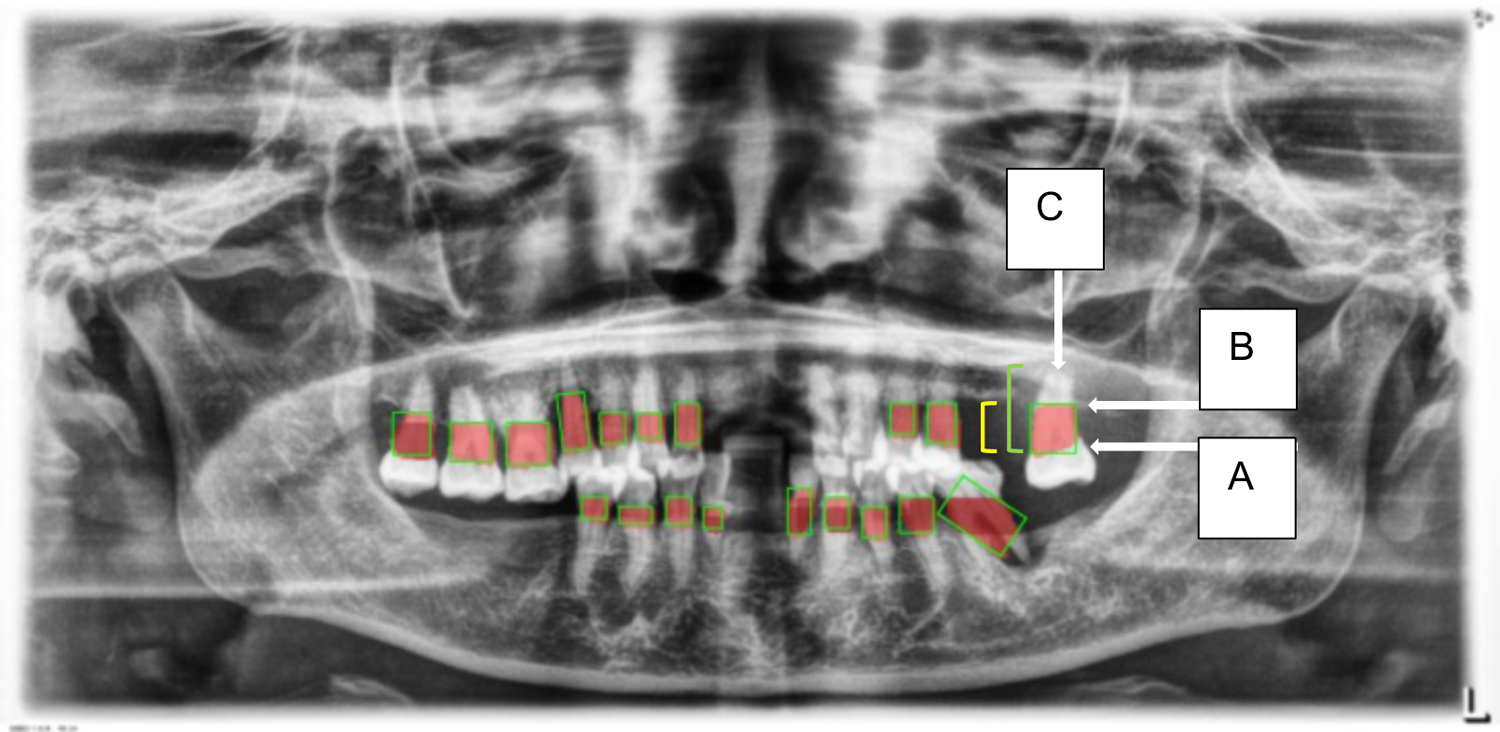

Localization and Classification: The model was trained to identify and localize the region between the cemento-enamel junction (CEJ) and the alveolar bone crest, producing bounding boxes or heat maps for further analysis (Figure 5).

- 4.Thresholding for Abnormality Detection (Severity of Periodontitis):

A thresholding mechanism will be devised to determine the extent of abnormality based on the width of the gap between the CEJ and the bone structure (

Figure 6). Teeth with gaps exceeding the predefined threshold (e.g., >2 mm) will be flagged as abnormally positioned. To calculate the percentage of bone loss, use the formula (

Figure 5

Image showing the predicted area between the CEJ and the alveolar bone crest (A), and teeth segmentation (B).

Figure 6

This figure illustrates an example of radiographic bone loss. The color coding for the lines is as follows: yellow denotes the distance from the cemento-enamel junction (CEJ) (A) to the alveolar bone crest level (B), green represents the distance from the CEJ to the root apex (C), and red boxes highlight the distance from the CEJ to the alveolar bone crest level.